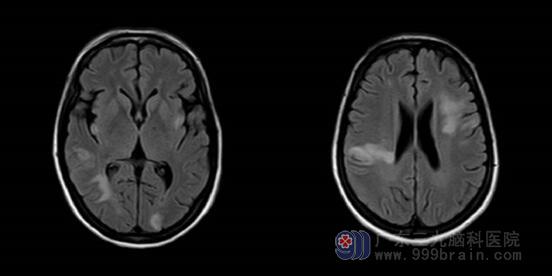

▲颅脑平扫+增强:双侧大小脑半球多发病变,需鉴别脑炎、脱髓鞘病变及血管源性病变。

▲DWI:双侧小脑半球、双侧大脑半球、桥脑右侧多发脑梗塞(亚急性期),左侧额叶异常信号影。